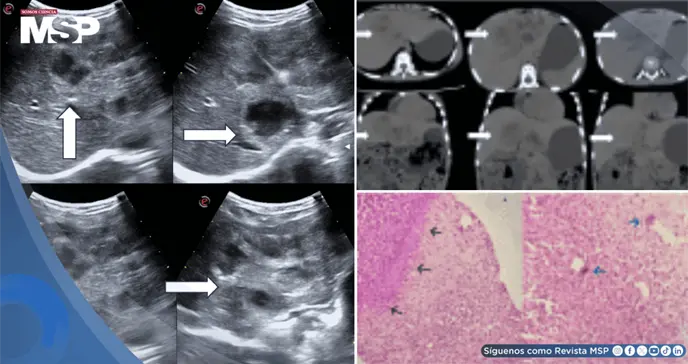

Como parte del protocolo diagnóstico, se realizó una ecografía abdominal completa que evidenció la presencia de lesiones hipoecoicas de características sólido-quísticas conglomeradas, localizadas específicamente en el lóbulo caudado y el lóbulo hepático izquierdo. La evaluación mediante Doppler color demostró que estas lesiones carecían de vascularidad significativa.

Para obtener una caracterización más detallada, se procedió con una tomografía computarizada con contraste del abdomen, la cual reveló una lesión hipodensa multiloculada conglomerada que presentaba realce del borde periférico, localizada en el lóbulo izquierdo y el lóbulo caudado, acompañada de una dilatación mínima de la radícula biliar adyacente, probablemente secundaria al efecto de masa.

Adicionalmente, se observó el agrandamiento de algunos ganglios linfáticos peripancreáticos y retroperitoneales.

Se planificó y ejecutó una biopsia guiada por ultrasonido bajo anestesia local, obteniéndose tres núcleos de tejido de la lesión hepática que fueron enviados para examen histopatológico.

Las secciones de tejido, teñidas con hematoxilina y eosina, revelaron bajo microscopía núcleos fragmentados de parénquima hepático que mostraban un granuloma necrosante con numerosos cristales de Charcot-Leyden dentro de densos infiltrados inflamatorios compuestos por linfocitos, células plasmáticas y eosinófilos.

Estos hallazgos histopatológicos fueron compatibles con el diagnóstico de absceso eosinofílico, confirmando así el diagnóstico de larva migratoria visceral hepática.